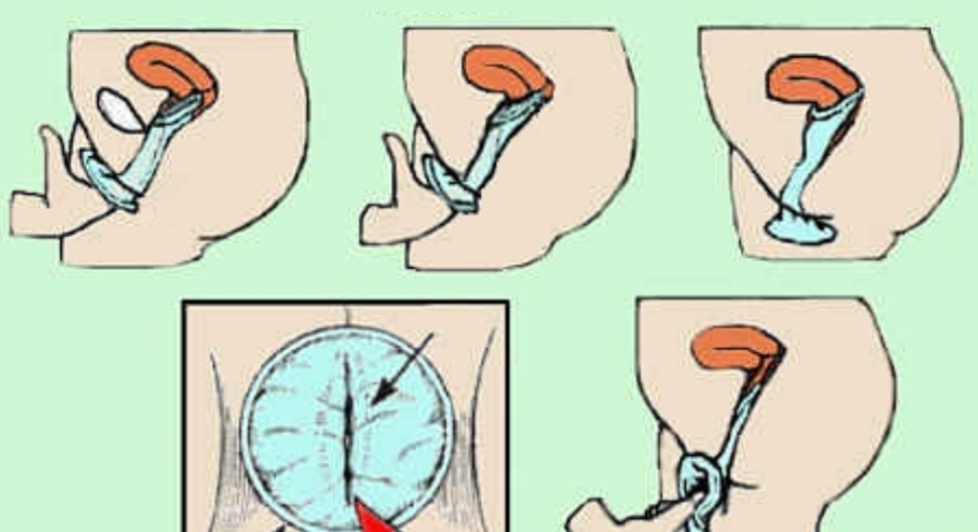

人工陰道漫畫的

治療中人工陰道漫畫

人工陰道漫畫

治療中人工陰道

治療中人工陰道漫畫

治療中人工陰道的

正在治療的人工陰道

治療中的人工陰道的

治療中的人工陰道

正常人工陰道的

正常人工陰道

幼兒人工陰道

正常的人工陰道的

正常的人工陰道

正常女性人工陰道

人工陰道治療中的

人工陰道作用

人工陰道治療

人工陰道治療前期

人工陰道治療前後